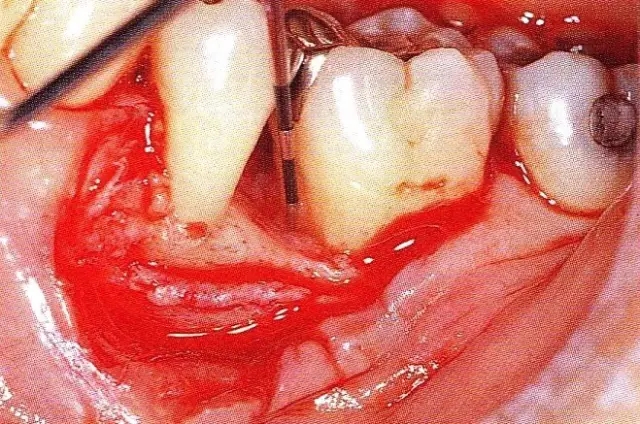

640.webp (2).jpg

▲圖7-3  將posterior interproximal類型的非吸收性覆膜修整后進(jìn)行垂直懸吊縫合做固定。垂直懸吊縫合后,確定覆膜是否會動搖,再將齦瓣與之緊密縫合。